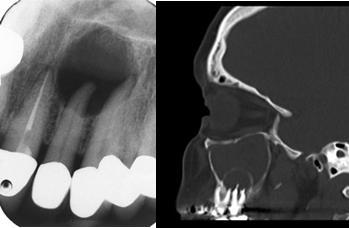

根尖周炎:冷热试验; CBCT、口腔全景片PAR 或 根尖拍片OP

7、牙科常见的检查包括:CBCT(相比普通鼻窦CT能更好的显示牙齿问题,下图);口腔全景片,根尖X拍照,牙髓温度测试